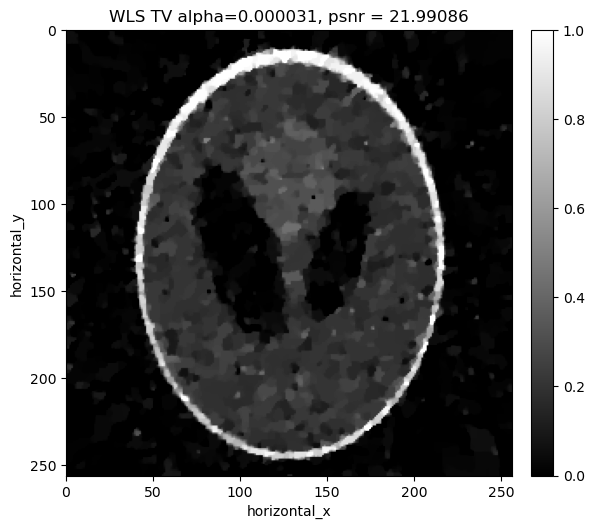

Reconstructing the noisy data using least squares with Total Variation regualrisation#

Similar to the least squares cas, in addition to the weighted least square term, we considered a Total Variation Regulariser. We minimize:

\[||Y-Ax||_{W}^{2} + \alpha \, TV(x)\]

where \(\alpha\) is the regularization parameter that balances the two terms. Again we search a range of values of \(\alpha\) to find the best one for the data.

../../_images/demos_LS_WLS_KL_TotalVariation_40_3.png

../../_images/demos_LS_WLS_KL_TotalVariation_40_4.png

alpha=0.000031, psnr= 21.991